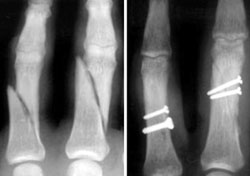

Fractures are seen in the phalanges of two fingers (left). The image on the right shows how the fractures are repaired with screws.

Reproduced with permission from Kozin SH, Thoder JJ, Lieberman G: Operative Treatment of Metacarpal and Phalangeal Shaft Fractures. J Am Acad Orthop Surg 2000;8:111-121.